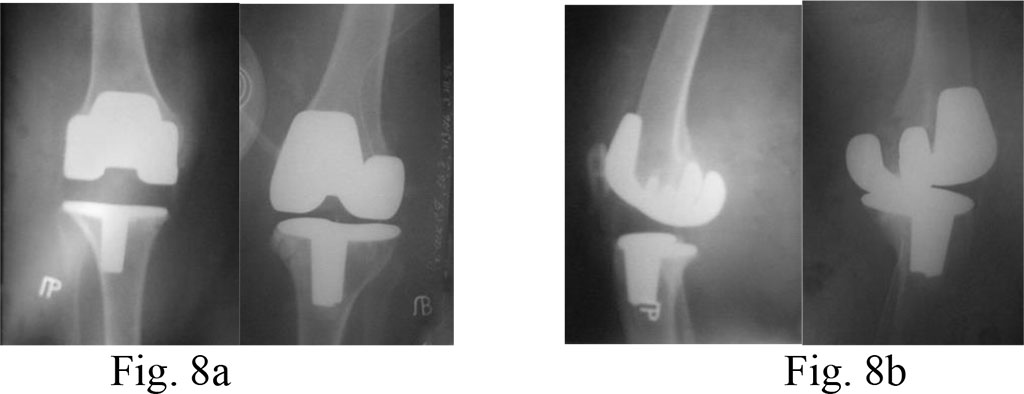

Diagnosis: bilateral deforming gonarthrosis stage 4; varus deformities of both knees.

Surgical treatment: bilateral total knee arthroplasty with PCL preservation.

On the right, we carried out tibial resection on the level of the lower edge of the defect and applied a large tibial insert (21 mm). On the left, resection of the tibial bone was on the level of the upper edge of the lesion, than filled with bone cement and a tibial insert of a minimal size (9 mm) (Fig. 7a, b and 8a, b)